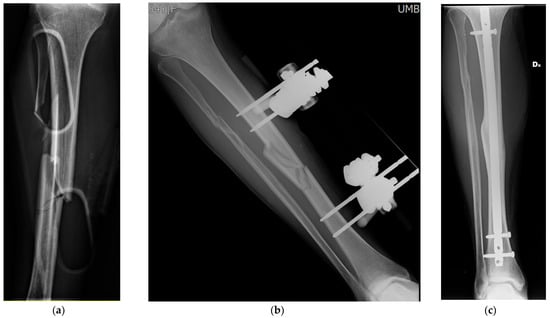

- Malizos, K.; Blauth, M.; Danita, A.; Capuano, N.; Mezzoprete, R.; Logoluso, N.; Drago, L.; Romanò, C.L. Fast-resorbable antibiotic-loaded hydrogel coating to reduce post-surgical infection after internal osteosynthesis: A multicenter randomized controlled trial. J. Orthop. Traumatol. 2017, in press. [Google Scholar] [CrossRef] [Green Version]

- De Meo, D.; Cannari, F.M.; Petriello, L.; Persiani, P.; Villani, C. Gentamicin-Coated Tibia Nail in Fractures and Nonunion to Reduce Fracture-Related Infections: A Systematic Review. Molecules 2020, 25, 5471. [Google Scholar] [CrossRef]

- Pinto, D.; Manjunatha, K.; Savur, A.D.; Ahmed, N.R.; Mallya, S.; Ramya, V. Comparative study of the efficacy of gentamicin-coated intramedullary interlocking nail versus regular intramedullary interlocking nail in Gustilo type I and II open tibia fractures. Chin. J. Traumatol. 2019, 22, 270–273. [Google Scholar] [CrossRef]

- Metsemakers, W.-J.; Reul, M.; Nijs, S. The use of gentamicin-coated nails in complex open tibia fracture and revision cases: A retrospective analysis of a single centre case series and review of the literature. Injury 2015, 46, 2433–2437. [Google Scholar] [CrossRef]

- Moghaddam, A.; Weis, J.; Haubruck, P.; Raven, T.F.; Addali, A.; Schmidmaier, G. Evaluation of the clinical use of the ETN PROtect® in non-union therapy. Injury 2019, 50, 32–39. [Google Scholar] [CrossRef]